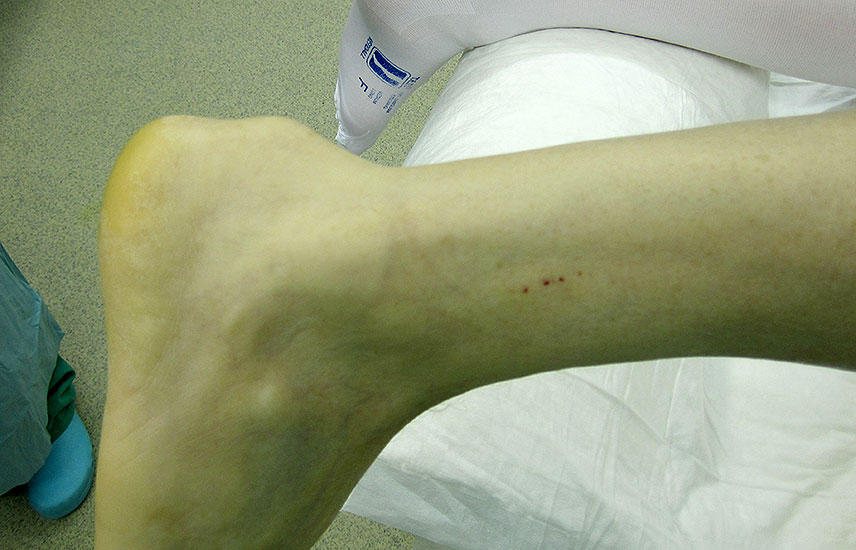

Abbildung 1

Die klassische traumatische Achillessehnenruptur wird von den Betroffenen meist eindrücklich wahrgenommen. Ein peitschenartiger Knall gefolgt von einem Waden- und/ oder Fersenschmerz, sowie der (partielle) Funktionsverlust führt sie in die weitere ärztliche Behandlung. Hier ist die Anamnese meist das zielführende Diagnostikum. Bei der klinischen Untersuchung präsentiert sich eine tast- und sichtbare Dehiszenz, begleitet von einem lokalen Hämatom. Der Einbeinzehenspitzenstand ist in der Regel nicht mehr möglich.